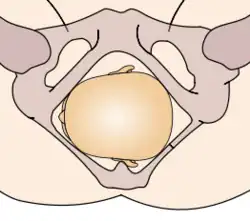

The vertex presentations are further classified according to the position of the occiput, both right, left, or transverse and anterior or posterior:

- Left Occipito-Anterior (LOA), Left Occipito-Posterior (LOP), Left Occipito-Transverse (LOT)

- Right Occipito-Anterior (ROA), Right Occipito-Posterior (ROP), Right Occipito-Transverse (ROT)

The occipito-anterior position is ideal for birth; it means that the baby is lined up so as to fit through the pelvis as easily as possible. The baby is head down, facing the spine, with their back anterior. In this position, the baby's chin is tucked onto their chest, so that the smallest part of their head will be applied to the cervix first. The position is usually "Left Occiput Anterior", or LOA. Occasionally, the baby may be "Right Occiput Anterior", or ROA.[5]